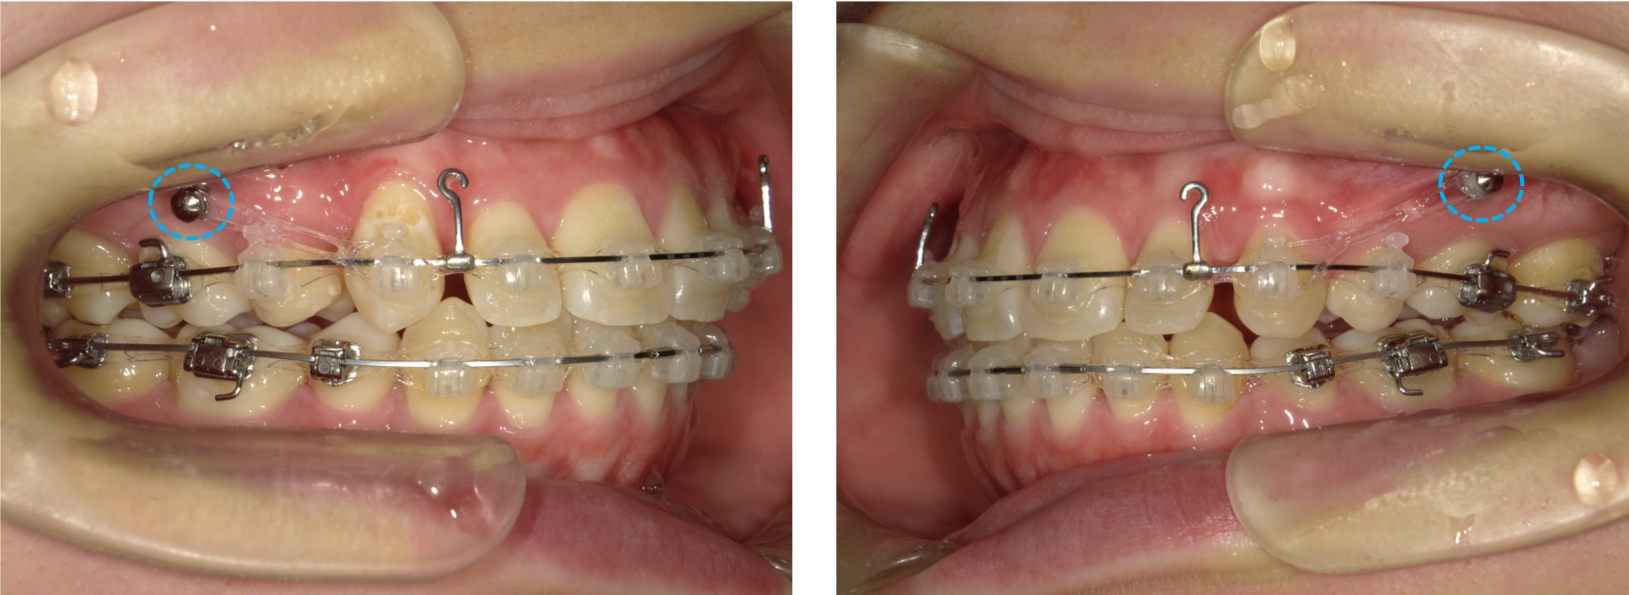

歯列が整ったあと、上顎頬側5番と6番の間にアンカースクリュー(水色の◯の箇所)を併用し、前歯を後方へ移動させました。

※関連記事:アンカースクリュー特集>>